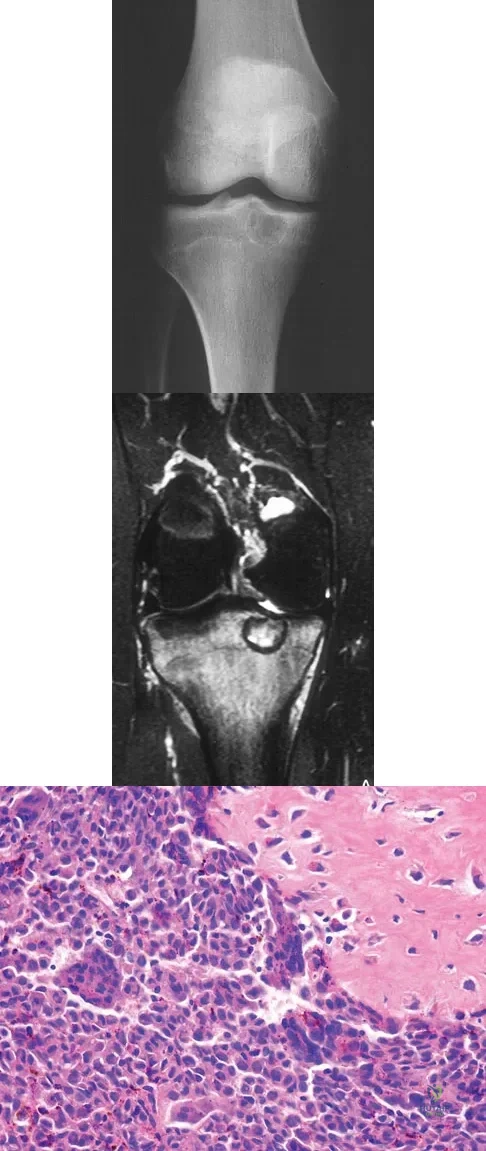

A 16-year-old boy has had left knee pain and swelling after sustaining a minor twisting injury while playing basketball 2 weeks ago. Figures 5a through 5e show the radiograph, MRI scans, and biopsy specimens. What is the most likely diagnosis?

Explanation